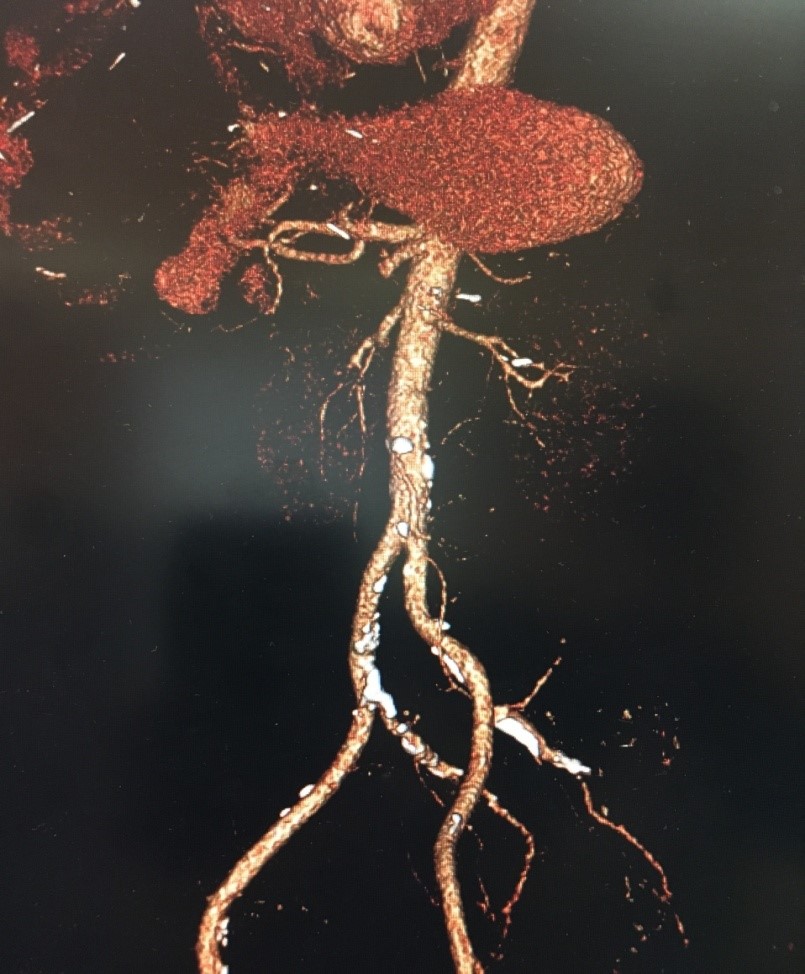

Компьютерная томография органов брюшной полости и забрюшинного пространства с внутривенным болюсным контрастированием выполнена: КТ признаки артериального тромбоза в крупных и мелких ветвях в бассейне ВБВ (Рис. 1). Артериальный тромбоз дистальных отделов селезеночной артерии, ветвей печночной артерии. Инфаркт селезенки.

Рисунок 1. МСКТ ангиография брюшной аорты. Стрелкой указана тромбированная ВБА.